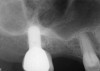

Fig. 21  Pretreatment radiograph suggesting more than 2 mm of subantral, alveolar bone.

Figure 21

A patient who had received treatment 10 years ago for implants in the mandibular arch said her general dentist wanted to place an implant in site No. 3, using a hammer. Although that clinician believed the site had sufficient bone based on a periapical x-ray findings (Figure 21), the findings from a cross-sectional computed tomography scan helped determine that she had less than 3 mm of bone in the ridge (Figure 22). Froum et al14 and Tarnow et al15 both demonstrated the efficacy of combining rhBMP-2/ACS with mineralized bone allograft in sinus graft procedures. Marx et al16 demonstrated the combination of this growth factor with mineralized allograft and PRP to reconstruct severe maxillary defects. Given the 4 mm of minimal requirement for simultaneous implant placement, the author performed a lateral window sinus graft. An absorbable collagen sponge hydrated with rhBMP-2 was combined with mineralized bone allograft and used to obturate the site after reflection of the Schneiderian membrane along the medial sinus wall. A portion of the rhBMP-2/ACS was adapted over the grafted window osteotomy (Figure 23). After healing for approximately 5 months, the patient received a computer-guided implant surgery (Figure 24). The implant was restored with a screw-retained crown after a healing period of approximately 3 months.